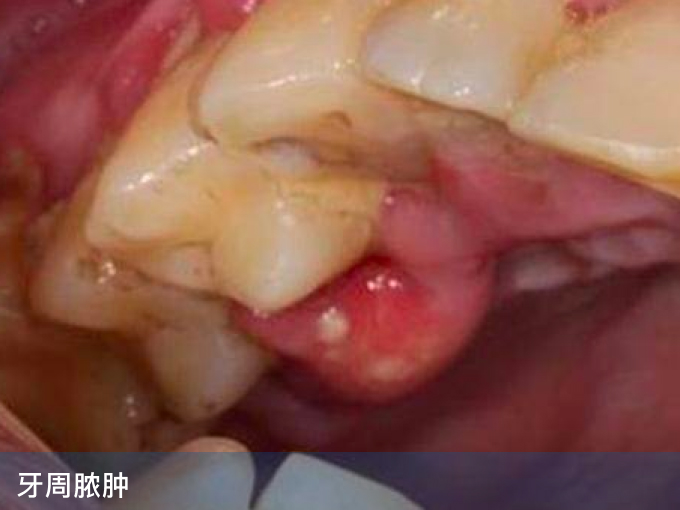

1、牙周脓肿:口腔卫生不良,导致大量牙菌斑和牙结石堆积在牙周组织,长期可导致牙周炎,出现牙周袋,牙周袋内的脓液大量淤积,可导致牙周脓肿,表现为红色软肉包,有时中间可发白或发黄,破溃可由脓液流出,伴有疼痛以及臭味,需要由医生进行切开排脓,配合龈上洁治和龈下刮治。